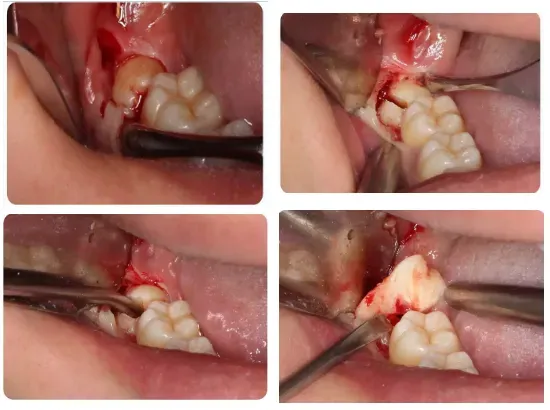

4、其他埋藏牙齿的阻力分析及手术设计;

●上颌阻生第三磨牙的阻力分析及手术设计

●通过病例讲解上颌阻生第三磨牙的微创拔除方法

●通过病例讲解阻生尖牙、前磨牙、磨牙、多生牙的微创拔除方法